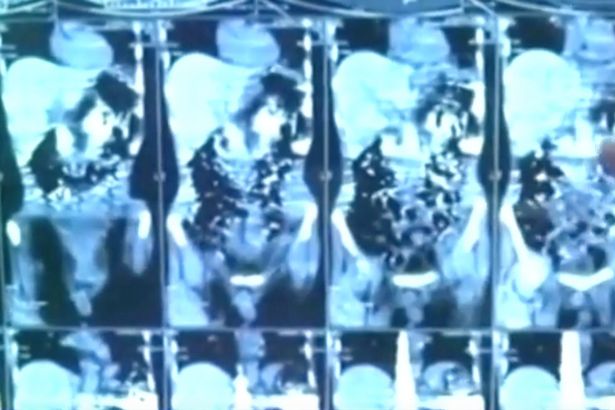

Các ảnh chụp X-quang dạ dày của bệnh nhân khiến các bác sĩ kinh ngạc khi nhìn thấy hơn 40 mảnh kim loại.

Các bác sĩ đã giải phẫu và lấy ra số dao người này đã nuốt suốt hơn 2 tháng qua.

Bác sĩ Jatinder Malhotra, giám đốc điều hành bệnh viện ở Amritsar cho biết, đây không phải là một ca bệnh ‘bình thường’, và tình trạng bệnh nhân vẫn rất ổn sau khi phẫu thuật.